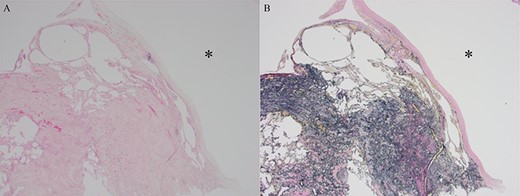

Histopathological findings showing a pulmonary bulla (asterisk in (A) and (B)). (A) Hematoxylin-Eosin stain. (B) Elastica van Gieson stain.

The histopathological findings of the resected lung specimen could not indicate an association between the cause of pneumothorax and abnormal blood vessels in our patient. The multiple bullae on the bilateral apical lungs had presented before pneumothorax onset, indicating that the spontaneous pneumothorax occurred with no specified etiology in our patient.

recurrent intermittent epistaxis every few months and was monitored for PAVMs using computed tomography (CT) examinations every 6 months. He had a family history of HHT in his father and grandfather. After systemic examinations, he was diagnosed with HHT because he met the diagnostic criteria, including the presence of PAVM, recurrent epistaxis, and a family history of HHT, although genetic testing was not performed. A chest CT scan showed a left pneumothorax and apical bullae on both sides of the upper lobe (Fig. 1). In addition, a total of six PAVMs (four in the right lung, two in the left lung) were shown on the chest CT (Fig. 2). All PAVMs were located peripherally with the largest one being 3 mm in diameter. No AVM was detected in the brain or abdomen on CT. He was treated conservatively and then pneumothorax was improved. Six months later, the patient complained of cough and was diagnosed with pneumothorax by chest X-ray. To prevent the recurrence of the pneumothorax, the patient was offered video-assisted thoracic surgery. Intraoperatively, apical bullae and multiple telangiectasias were identified under the visceral pleura (Fig. 3). We performed wedge resection of the left upper lobe including the apical bullae. The postoperative histopathological findings of the resected specimen revealed pulmonary bullae (Fig. 4). The postoperative course was uneventful, and the patient was discharged on postoperative Day 2. He underwent catheter embolization for PAVMs in another hospital. His SpO2, which was measured before catheter embolization, was 97% on room air. There was no remarkable change in SpO2 after the intervention. No recurrence of the pneumothorax was observed during a 3-year follow-up.